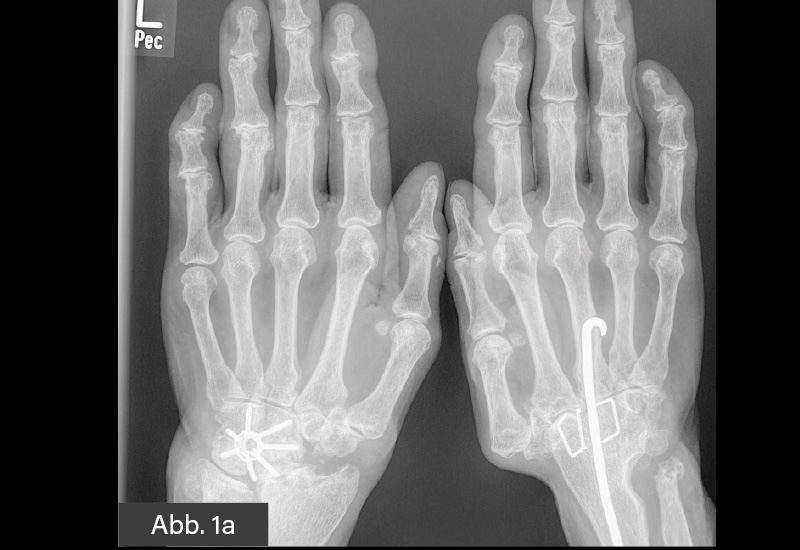

KLINISCHER BEFUND: 160,5 cm, 60 kg. Gelenkstatus: Versteifung des rechten Handgelenks. Deformität im Bereich des gesamten Handskelettes bds. Faustschluss bds. möglich. Derbe Auftreibungen und z. T. Fehlstellungen an den Fingerendgelenken D2 und D5. Druckschmerz am medialen Gelenkspalt Kniegelenke bds. Hallux valgus-Fehlstellung im Vorfußbereich, linksbetont. Spreizfuß. Aufgebrauchtes Quergewölbe.

LABOR: Hb 13,0 g/dl, CRP <5 mg/l., BKS 28/h, Leukos 6.200/µl, RF 167 IU/ml, ccP-Ak >500, ANA 1:320.

BILDGEBENDE DIAGNOSTIK: Röntgen (s. u.)

DIAGNOSE: Fortgeschrittene destruierende RA mit destruiertem Carpus bds.